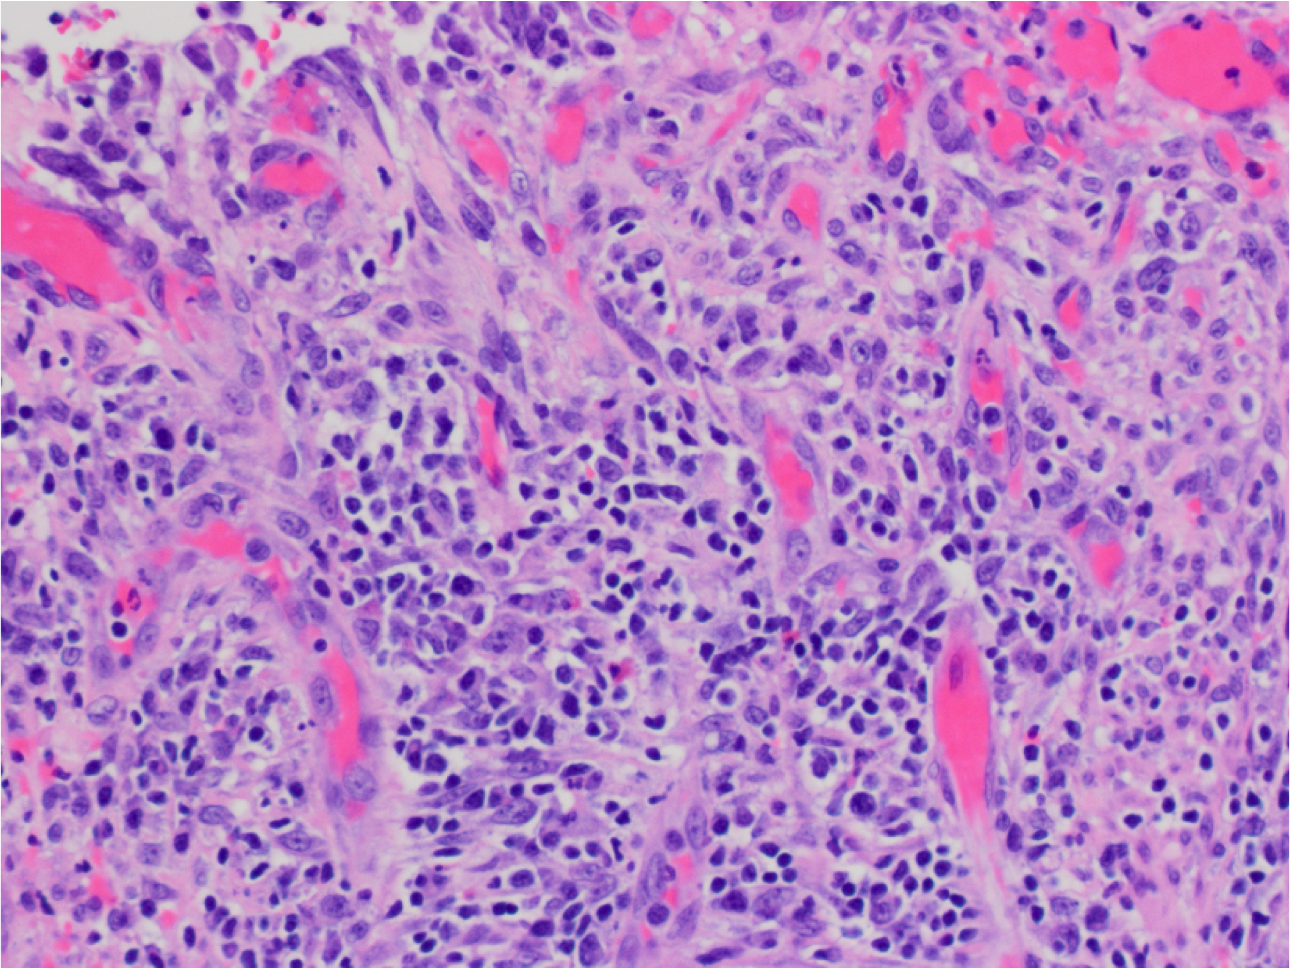

What’s this?

Gastric Ulcer

Underlying granulation tissue -repetitive pattern of capillaries containing RBCs, fibroblasts (top) and inflammatory cell infiltrate (middle and bottom)